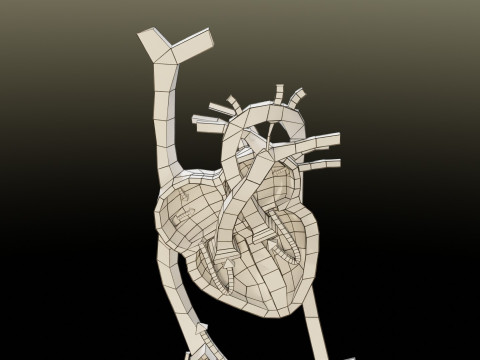

The model meshes include adult circulation versus circulation in Tetralogy of Fallot (TAF), arrow labels and text labels. The blood flow in a patient with Tetralogy of Fallot is outlined in this model. To contrast it to normal blood circulation a separate model of normal circulation is included. The Tetralogy of Fallot (OVER RIDING OF AORTA, PUL STENOSIS, VENTRICULAR SEPTAL DEFECT, RIGHT VENTRICULAR HYPERTROPHY), fossa, ligament teres , venosus, and arteriosus are duly depicted with proper labelling and blood flow directional arrows. Excellent model for teaching, demonstration and knowlegde of human body. The models include both procedural and image textures blend files separately. The texture file include diffuse, roughness and normal png and jpeg based on non overlapping UV maps.